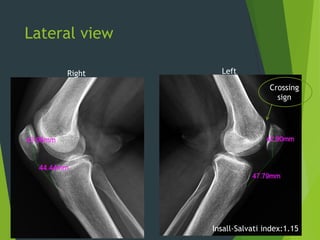

Lateral view

Crossing

sign

Insall-Salvati index:1.15

Right Left